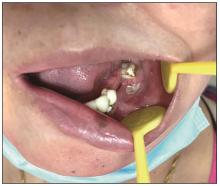

EB病毒阳性弥漫性大B细胞淋巴瘤(EBV+ DLBCL)是一种罕见的侵袭性B细胞淋巴瘤,好发于老年人,预后不良,结外受累部位常见于胃肠道、皮肤、骨髓,发生在牙龈的EBV+ DLBCL非常罕见。EBV+ DLBCL在病理组织形态学和免疫表型上,与EB病毒阳性黏膜皮肤溃疡极其相似,明确诊断具有挑战性。本文报告了1例原先诊断为EB病毒阳性黏膜皮肤溃疡(EBVMCU)的病例,后经淋巴瘤基因重排技术确诊为EBV+ DLBCL患者的临床表现和病理组织学特征,以期加深对该疾病的认识,有助于此类恶性疾病的早期诊断与治疗。